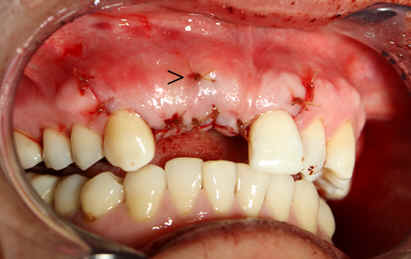

The adjusted stent fits well after raising the flap (Fig.14). Initial osteotomy is made using the stent. The osteotomy for #8 is located in the middle of the ridge labiolingually, whereas that for #7 is too lingual. Adjustment is made freehand. The final osteotomy is shown in Fig.15: 4.0 mm in diameter for #7 and 4.5 mm for #8. With direct vision (large exposure) and digital palpation, there is no perforation (not shown). There is concavity in the labial plate (arrowheads in Fig.15), which is corrected by connective tissue graft. The arrowhead in Fig.16 points to the suture that stabilizes the graft against the labial mucoperiosteal flap.